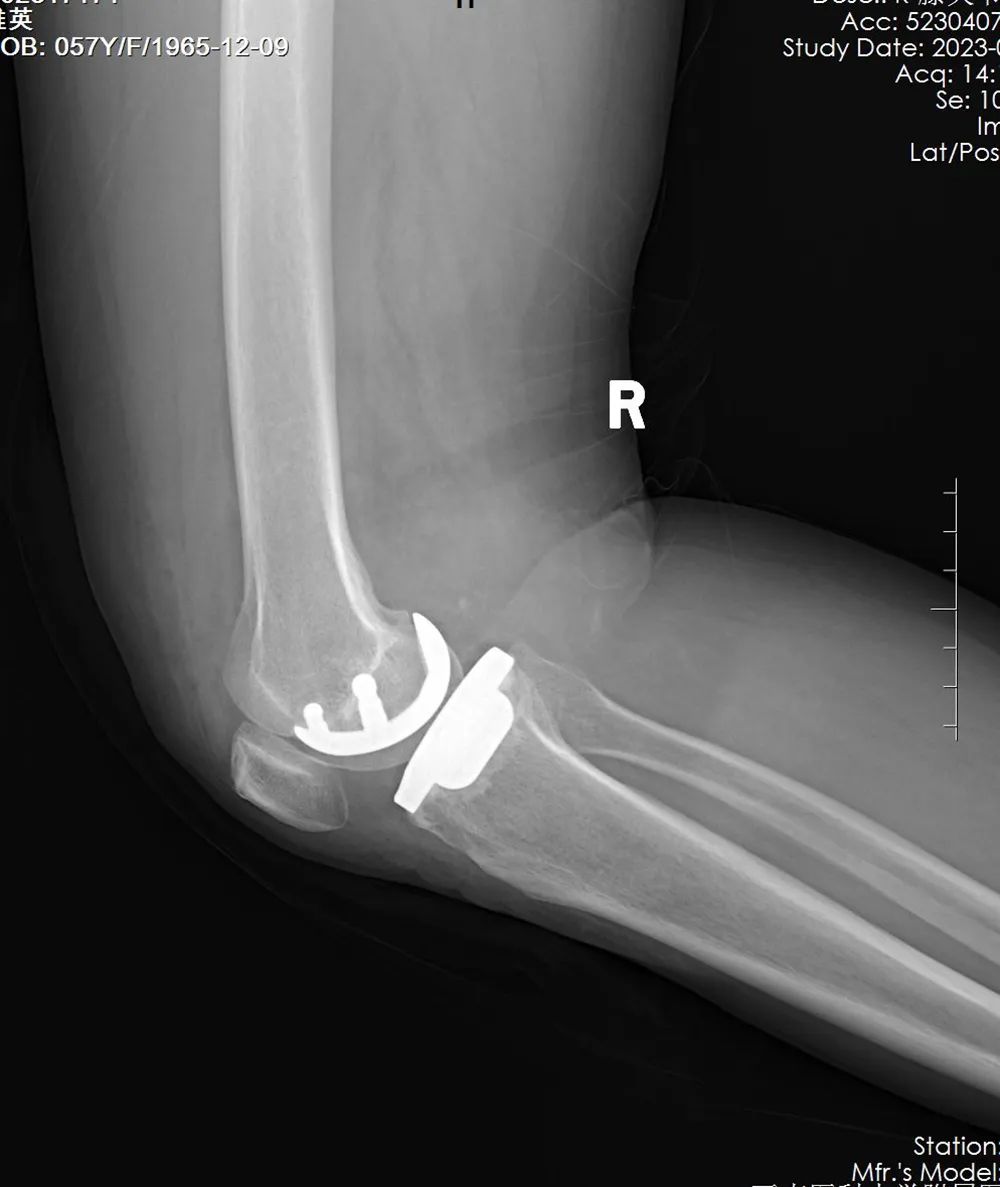

通过研磨试验(+),X光片及MRI检查,提示右膝关节外侧单间室骨关节炎,K-L分级Ⅲ级,有手术指征。经科室各位专家讨论后,排除手术禁忌症,在骨与关节外科主任李忠教授的指导下,骨科副主任尹一然副教授团队为患者实施了“右膝外侧人工单髁置换术”(LUKA),尽全力为张女士解除病痛的折磨。

手术进行了1个小时,很顺利。术后X光片显示,假体大小选择合适,假体位置精准植入,术后功能恢复良好。术后第一天,张女士的右膝关节屈曲达到120°以上,不用扶拐就能行走。

术后复查X光片